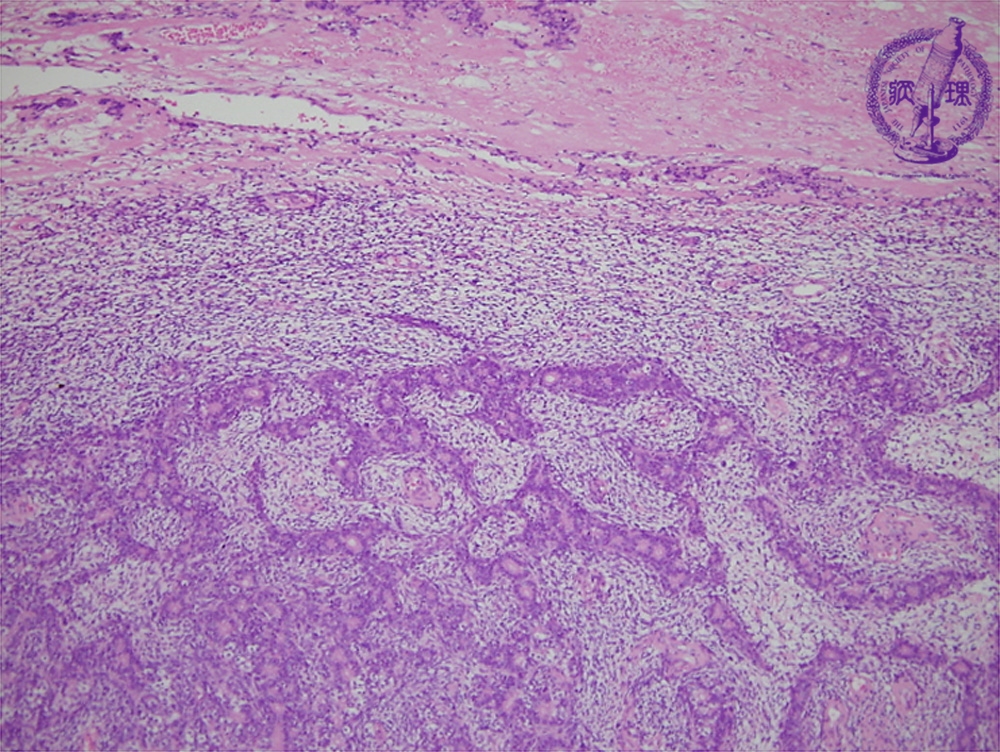

滑膜肉腫を他の軟部肉腫と区別するために、医師は生検を行います。これには、腫瘍から一部の組織を除去する外科的処置が含まれます。

その後、医療専門家が研究室で腫瘍サンプルを検査します。

生検の臨床検査で滑膜肉腫が確認された場合、次のステップには治療が含まれます。